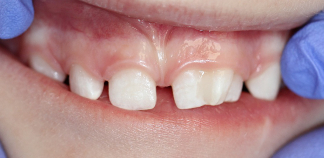

До лечения

Пришли с жалобой на кариес.

Пациенту 2 года.

Как лечили

Пролечен кариес трех сросшихся зубов под наркозом.

Лечение проведено за один визит.